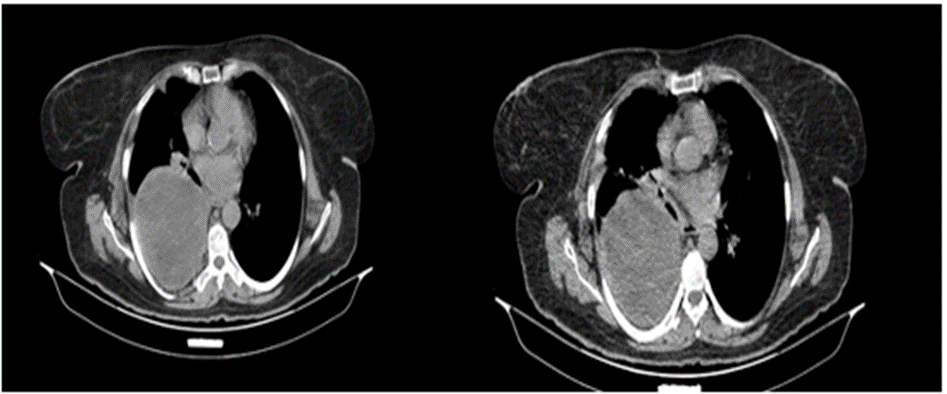

A 58-year-old woman was refered to our hospital with a history of recurrent right side chest wall pain ,cough ,night sweating ,hemoptysis and dyspnea for 4-6 weeks. A physical examination revealed respiratory sounds were decreased on the middle right side of chest. His complete blood count, erythrocyte sedimentation rate, CRP blood urea nitrogen (BUN) level, and creatinine level were normal and liver function tests (AST,ALT ,AKP and bilirubin ) and anti hydatid tests were normal . Poster anterior (PA) and lateral chest radiographs were performed . The PA chest radiograph (Figure 1)showed a well-defined 10- to 14-cm right paracardiac cystic mass located in the right middle zone of chest. The CT-scan showed a large well –defined hypo dense cystic mass measuring 112 mm is seen in superior segment of RUL.Sub segmental atelectasis also seen in right lung caused compressing. Left lung was normal . Figure 2(a,b,c,d,e,f,g,h,i) . In the CT –scan there was no invasion of the chest wall and others intrathoracic structures. CT images show no enlargement of lymph nodes and pleural effusion but lung parachymal was involved.The testes for hydatid cyst were negative .Ultrasonography of abdomen was normal . A classic right posterolateral thoracotomy in six intercostal space was performed. Around of cystic lesion was walling off with wet sponge with normal Saline (Fig 3). In the aspiration of the lesion there was a hemorrhagic dense viscous fluid .The cystic mass was completely removed without complications and free margin. On the operation time , macroscopic examination show hemorrhagic dense viscous fluid and debris was observed in the center of the lesion(Fig 4) Microscopic examination showed an encapsulated mesenchymal neoplasm composed of short fasciles of bland looking spindle cell which are diffusely positive for S100 and GEAP on immunohistochemically diagnosis was a schwannoma tumor. The patient was discharged on the 6 th postoperative day. The patient did not recurrence after 8 month of follow-up

Figure: 2 CT -scan A, B, C, D, E, F, G show solid cystic lesion.